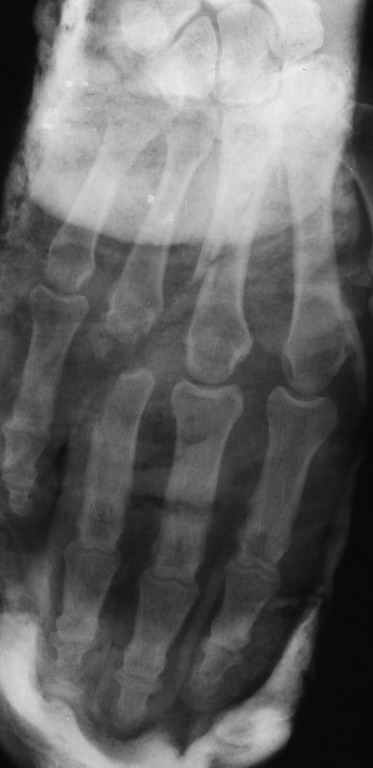

Диагноз на 15.07.05: Стойкая смешанная дермотеногенная контрактура 3,4 пальца правой кисти 3 степени.

-- сделать рентгенограмму;

Диагноз: Стойкая Смешанная дермотеногенная контрактура 3,4 пальца правой кисти.

Судя по выписному эпикризу, рентгенограммам и фотографиям, пациенту

показано этапное лечение.